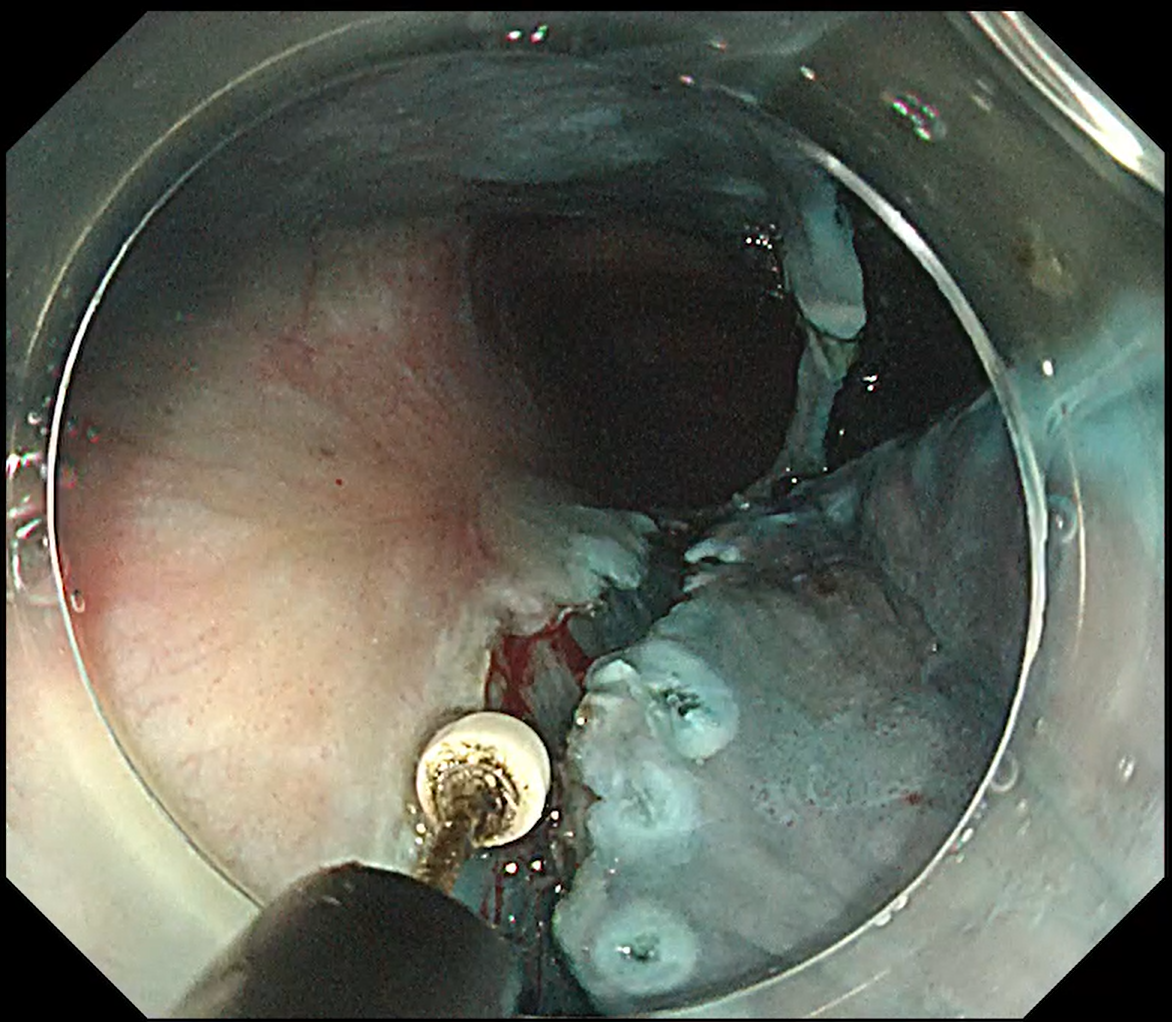

A 50 mm laterally spreading tumour in the ascending colon was addressed (Fig. 13). With ITknife nano the fundamental manoeuvre is “inside to outside”, advancing toward the lumen (Fig. 14).

Even when a large vessel or ambiguous fold obscured the plane, safe dissection was possible by first creating a small ‘hold’ on the vessel side – lightly melting the blue submucosa with the insulated tip – then continuing the inside to outside approach (Fig. 15, Movie 3).

Should gravity or scope instability slow progress, traction is applied to stand up the submucosa. Once the tissue is standing, rapid dissection can be performed with the ITknife nano without altering patient position, completing the resection efficiently.